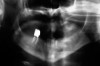

Under the sextant approach, one quadrant is treated and the patient is left to heal for 2 months before proceeding to any additional quadrants. While the patient heals, a 10-day course of antibiotics and 2 months of twice-daily chlorhexidine rinsing may be prescribed. Figure 4 shows a patient who was taking oral bisphosphonates for 3 years and was treated with the sextant approach. As seen in the radiograph, the patient has one molar in the lower right quadrant. This tooth was extracted and the patient was given 2 months to heal (Figure 5 and Figure 6). The patient was placed on antibiotics and chlorhexidine rinse. After 2 months, no signs of BRONJ were observed, and the anterior teeth were scheduled for extraction. They were extracted as atraumatically as possible, and the site was sutured (Figure 7 and Figure 8).The patient then was given another 2 months to heal, following the previous protocol. After 2 months of healing, no BRONJ was observed (Figure 9).

Figure 4  Radiograph of oral bisphosphonate user.

Figure 4